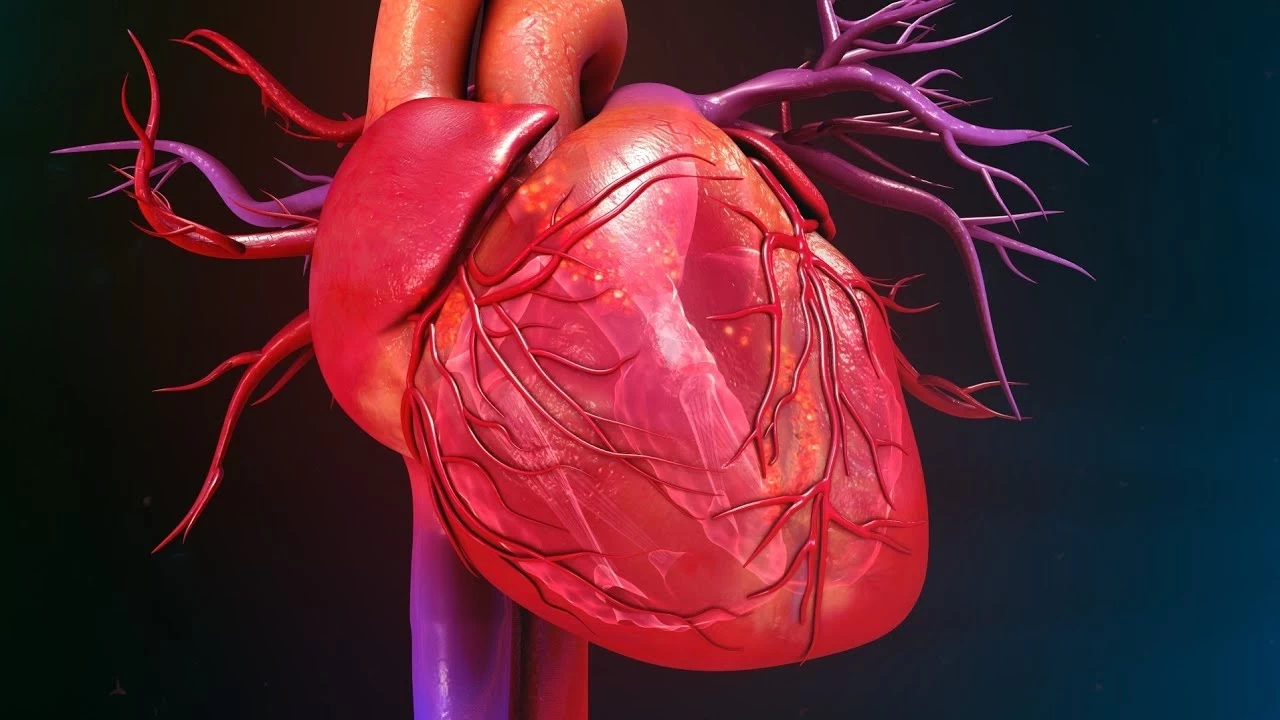

- Göğüs Ağrısı: Kalp krizinin en bilinen belirtisidir. Sıkışma, baskı veya ağrı hissi olarak tanımlanabilir.

- Nefes Darlığı: Efor sırasında veya dinlenirken ortaya çıkabilir. Kalbin yeterince kan pompalayamaması durumunda oluşur.

- Çarpıntı: Kalp atışlarının hızlı, düzensiz veya güçlü hissedilmesi. Anksiyete veya aşırı kafein tüketiminden kaynaklanabileceği gibi ciddi bir sorunun belirtisi de olabilir.

- Baş Dönmesi ve Bayılma: Bu belirtiler, beyin kan akışının azalmasıyla ortaya çıkabilir ve acil müdahale gerektirir.

- Şişlik: Ayaklarda, bacaklarda veya karında sıvı birikmesi, kalp yetmezliğinin bir işareti olabilir.

- Yorgunluk: Aşırı yorgunluk, kalp hastalığının gizli bir belirtisi olarak kendini gösterebilir.

- Terleme: Normalden fazla terleme, özellikle dinlenme halinde meydana geliyorsa dikkat edilmelidir.

- Mide Bulantısı ve Kusma: Bu belirtiler, kalp problemlerinin belirtisi olarak ortaya çıkabilir.

- Çene veya Sırt Ağrısı: Kalp krizi sırasında ağrı genellikle çene veya sırta yayılabilir.

- Egzersiz Toleransında Azalma: Normal aktiviteleri yaparken yorgunluk hissi, kalp sağlığı açısından risk işareti olabilir.

- Hızlı veya Düzensiz Nabız: Bu durum, kalp ritminde anormalliklerin belirtisi olabilir.